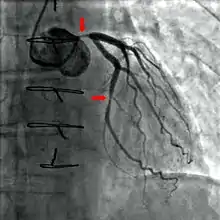

Coronary catheterization is one of the several cardiology diagnostic tests and procedures. Specifically, through the injection of a liquid radiocontrast agent and illumination with X-rays,[1] angiocardiography allows the recognition of occlusion, stenosis, restenosis, thrombosis or aneurysmal enlargement of the coronary artery lumens; heart chamber size; heart muscle contraction performance; and some aspects of heart valve function. Important internal heart and lung blood pressures, not measurable from outside the body, can be accurately measured during the test. The relevant problems that the test deals with most commonly occur as a result of advanced atherosclerosis – atheroma activity within the wall of the coronary arteries. Less frequently, valvular, heart muscle, or arrhythmia issues are the primary focus of the test.

During coronary catheterization (often referred to as a cath by physicians), blood pressures are recorded and fluoroscopy (X-ray motion picture) shadow-grams of the blood inside the coronary arteries are recorded. In order to create the X-ray pictures, a physician guides a small tube-like device called a catheter, typically ~2.0 mm (6-French) in diameter, through the large arteries of the body until the tip is just within the opening of one of the coronary arteries. By design, the catheter is smaller than the lumen of the artery it is placed in; internal (intra-arterial) blood pressures are monitored through the catheter to verify that the catheter does not block blood flow (as indicated by "dampening" of the blood pressure).

The catheter is itself designed to be radiodense for visibility and it allows a clear, watery, blood compatible radiocontrast agent, commonly called an X-ray dye, to be selectively injected and mixed with the blood flowing within the artery. Typically 3–8 cc of the radiocontrast agent is injected for each image to make the blood flow visible for about 3–5 seconds as the radiocontrast agent is rapidly washed away into the coronary capillaries and then coronary veins. Without the X-ray dye injection, the blood and surrounding heart tissues appear, on X-ray, as only a mildly-shape-changing, otherwise uniform water density mass; no details of the blood and internal organ structure are discernible. The radiocontrast within the blood allows visualization of the blood flow within the arteries or heart chambers, depending on where it is injected.

If atheroma, or clots, are protruding into the lumen, producing narrowing, the narrowing may be seen instead as increased haziness within the X-ray shadow images of the blood/dye column within that portion of the artery; this is as compared to adjacent, presumed healthier, less stenotic areas.